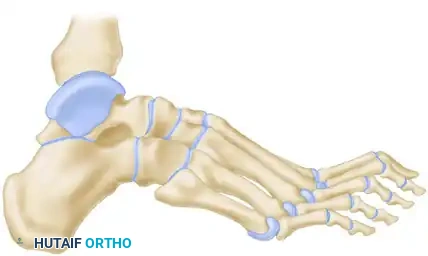

SURGICAL ANATOMY OF THE PERONEAL TENDONS

Understanding the spatial relationship of the peroneal tendons is paramount for safe harvest and routing.

- Proximal to the Fibula: The peroneus longus and brevis share a common synovial sheath within the retromalleolar groove.

- At the Fibula: Immediately posterior to the lateral malleolus, the peroneus longus lies anterior or superficial to the brevis tendon.

- Distal to the Fibula: This relationship changes as the tendons rotate; the brevis tendon becomes superficial and inserts onto the base of the fifth metatarsal.

Surgical Warning: The brevis tendon can be easily identified proximally because its muscle fibers extend much further distally on the tendon compared to the peroneus longus, which has no attached muscle at this level.